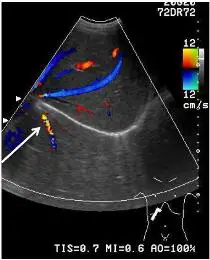

附圖為腹部都卜勒超音波圖,箭號所指為下列何者?

本題測驗超音波成像原理中的「鏡像假影」(mirror image artifact) 以及在 color Doppler (彩色都卜勒) 模式下,如何透過解剖位置與血流方向來鑑別肝臟內的 hepatic vein (肝靜脈) 與 portal vein (門靜脈)。

- 掃描視角與解剖對應:影像為腹部超音波的 color Doppler 掃描。觀察右下角的 body mark (體表標記),探頭放置於右側肋下緣 (subcostal approach) 並往頭側 (cranial) 掃描。

- 高回音反射面:影像中央有一條非常明亮的弧形高回音實線 (hyperechoic curved line),這是 diaphragm (橫膈膜)。

- 音場分佈:在 diaphragm 上方 (較靠近探頭的近端音場) 為 liver (肝臟) 實質組織;在 diaphragm 下方 (較遠離探頭的遠端音場),其實際解剖位置應為 lung (肺部) 與胸腔。由於正常肺部充滿空氣,超音波無法穿透,理論上不應出現真實的軟組織或血管結構。

- Color Doppler 血流特徵:

- 右側的 color map (色階卡) 顯示,紅色代表血流朝向探頭,藍色代表血流遠離探頭。請注意,流速上下限 (Scale) 僅設